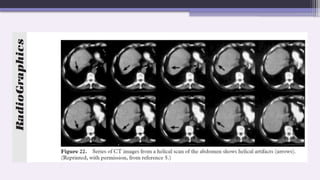

B. Helical Artifacts In Multisection scanning

1. Windmill artifact:

The typical windmill-like appearance of such artifacts is due to the fact that

several rows of detectors intersect the plane of reconstruction during the course

of each rotation.

As helical pitch increases, the number of detector rows intersecting the image

plane per rotation increases and the number of “vanes” in the windmill artifact

increases.

More complicated form of axial image distortion.

Seen in thin slice images reconstructed from high pitch helical multislice CT

images.

Type of aliasing artifact

The term windmill comes from the spiral appearance of shading artifact.

Regular equidistant streaks radiating from high-density foci

scattered throughout the soft tissues are depicted on the axial

CT image. The streak pattern rotates and continues from one

image to another. This is caused by inadequate sampling in

the z direction (aliasing). This artifact occurs when multiple

rows of detectors intersect the plane of reconstruction during

a rotation. The number of pairs in the windmill correspond to

the number of detectors intersecting the reconstructed image

plane.